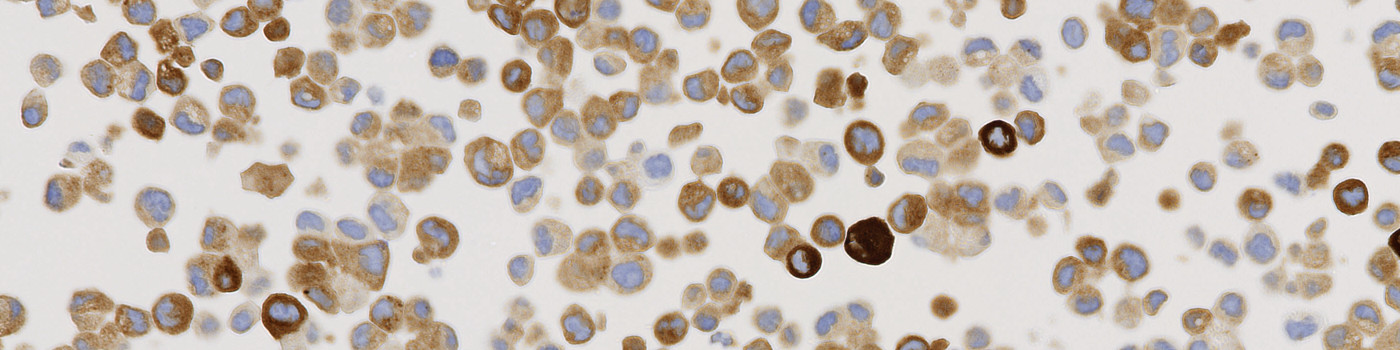

Positive cell line core, with strong cytoplasmic granular staining pattern.

The Staining Pattern of ROS1 Translocation will have a strong cytoplasmic granular staining observed in the positive cell line core. No cytoplasmic, granular staining pattern observed in the negative cell line core. Stained on the Automated Leica BOND stainer (Cell Signalling, D4D6, #3287).